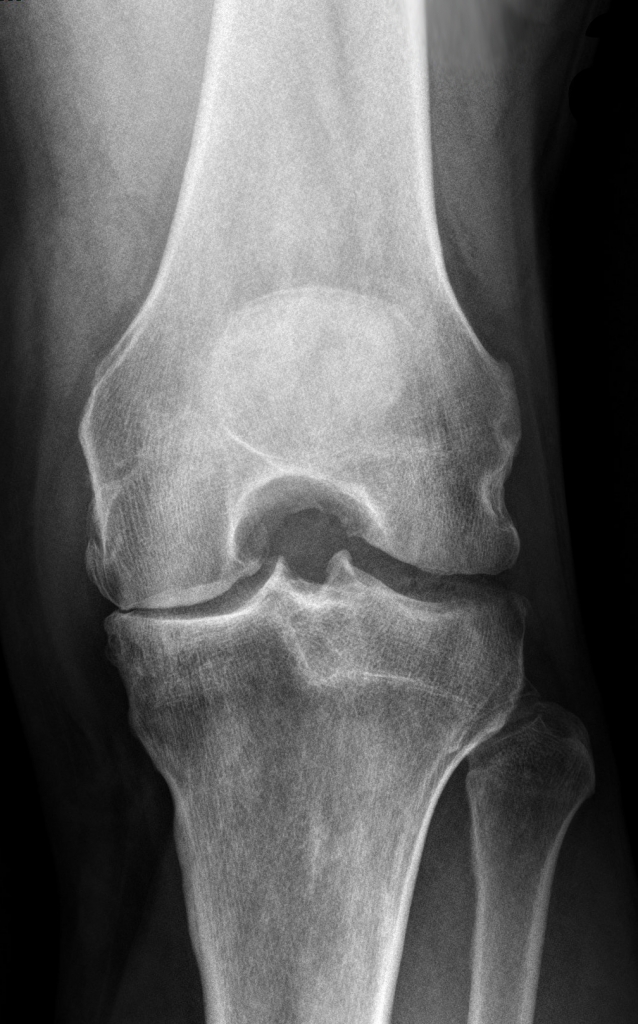

Die Hemischlittenprothese (oder Halbschlittenprothese) wird bei einseitiger Abnützung des Kniegelenkes auf der Innen- oder Aussenseite des Kniegelenkes eingesetzt. Kontraindikationen für die Implantation eines Halbschlittens sind die Arthrose des kontralateralen Kompartimentes, die rheumatoide Arthritis, eine Varus-Valgusdeformität von mehr 10°, ein Streckdefizit von mehr als 10° und die Kreuzbandinsuffizienz, insbesondere für die mobilen Gleitlager (erhöhte Luxationsgefahr).

Eine zuvor durchgeführte Untersuchung mittels Magnetresonanztomografie gibt Auskunft darüber, ob der Einsatz einer Halbschlittenprothese möglich ist.